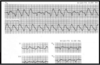

Interpret this EKG

Non-conducted PAC in Bigeminal rhythm